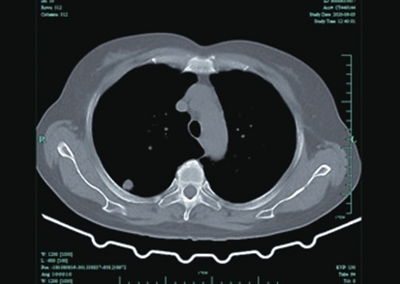

家住咸安青龙巷的金女士因宫颈癌,在武汉协和医院行规范治疗近一年后,于今年4月复查发现右肺上叶后段结节,性质待定。考虑到金大姐肺部结节较小,不到1cm,并且所处位置靠肩胛骨位置,想取活检明确病理难度极其高,武汉专家建议定期复查。由于病因尚不明确,金女士担心肿瘤复发,延误治疗,心情非常沉重且焦虑不安。

今年5月,在病友介绍下,金女士专程来到市中心医院,找到该院肿瘤科主任舒诚荣和章永医师,希望能得到两位医师的帮助。为了解除金大姐这块心病,两位医师在仔细阅片后,决定尝试使用自制带角度定位栅栏在CT引导下采取非共面经皮肺穿刺活检。

其中,该科所拥有的自制带角度定位栅栏在CT引导下经皮肺穿刺活检技术,是章永医师自行研发的一项新的应用技术,目前。该技术适用于肺部有病变的患者,如肿块,结节,软组织病变的患者,通过边做CT,并在自制带角度定位栅栏定位下,使得以往不易确定进针部位,能够精准确定肺部肿块进针穿刺位点,进行穿刺活检,取得肿块组织,送病理科行病理诊断,明确病变性质。